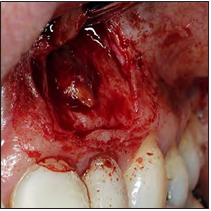

Después de la asepsia y antisepsia de la zona quirúrgica, se procedió con el bloqueo del nervio alveolar superior anterior y nervio nasopalatino (lidocaína 2% con epinefrina 1:80 000 Xylestesin, 3M ESPE, GERMANY), se realizó una incisión paramarginal con una hoja de bisturí #15 y posterior elevación del colgajo de espesor total. Ya expuesta la raíz (Fig. 2), se realizó la enucleación de la lesión, limpieza del campo quirúrgico mediante una fresa redonda de carburo tungsteno y rectificación del corte apical corrigiendo el bisel anterior por un bisel de 0° (Fig. 3). Con una gasa estéril impregnada de anestésico con vaso constrictor, se aplicó para el control de la hemorragia.

Figura 3. Apicectomía y enucleación de la lesión.